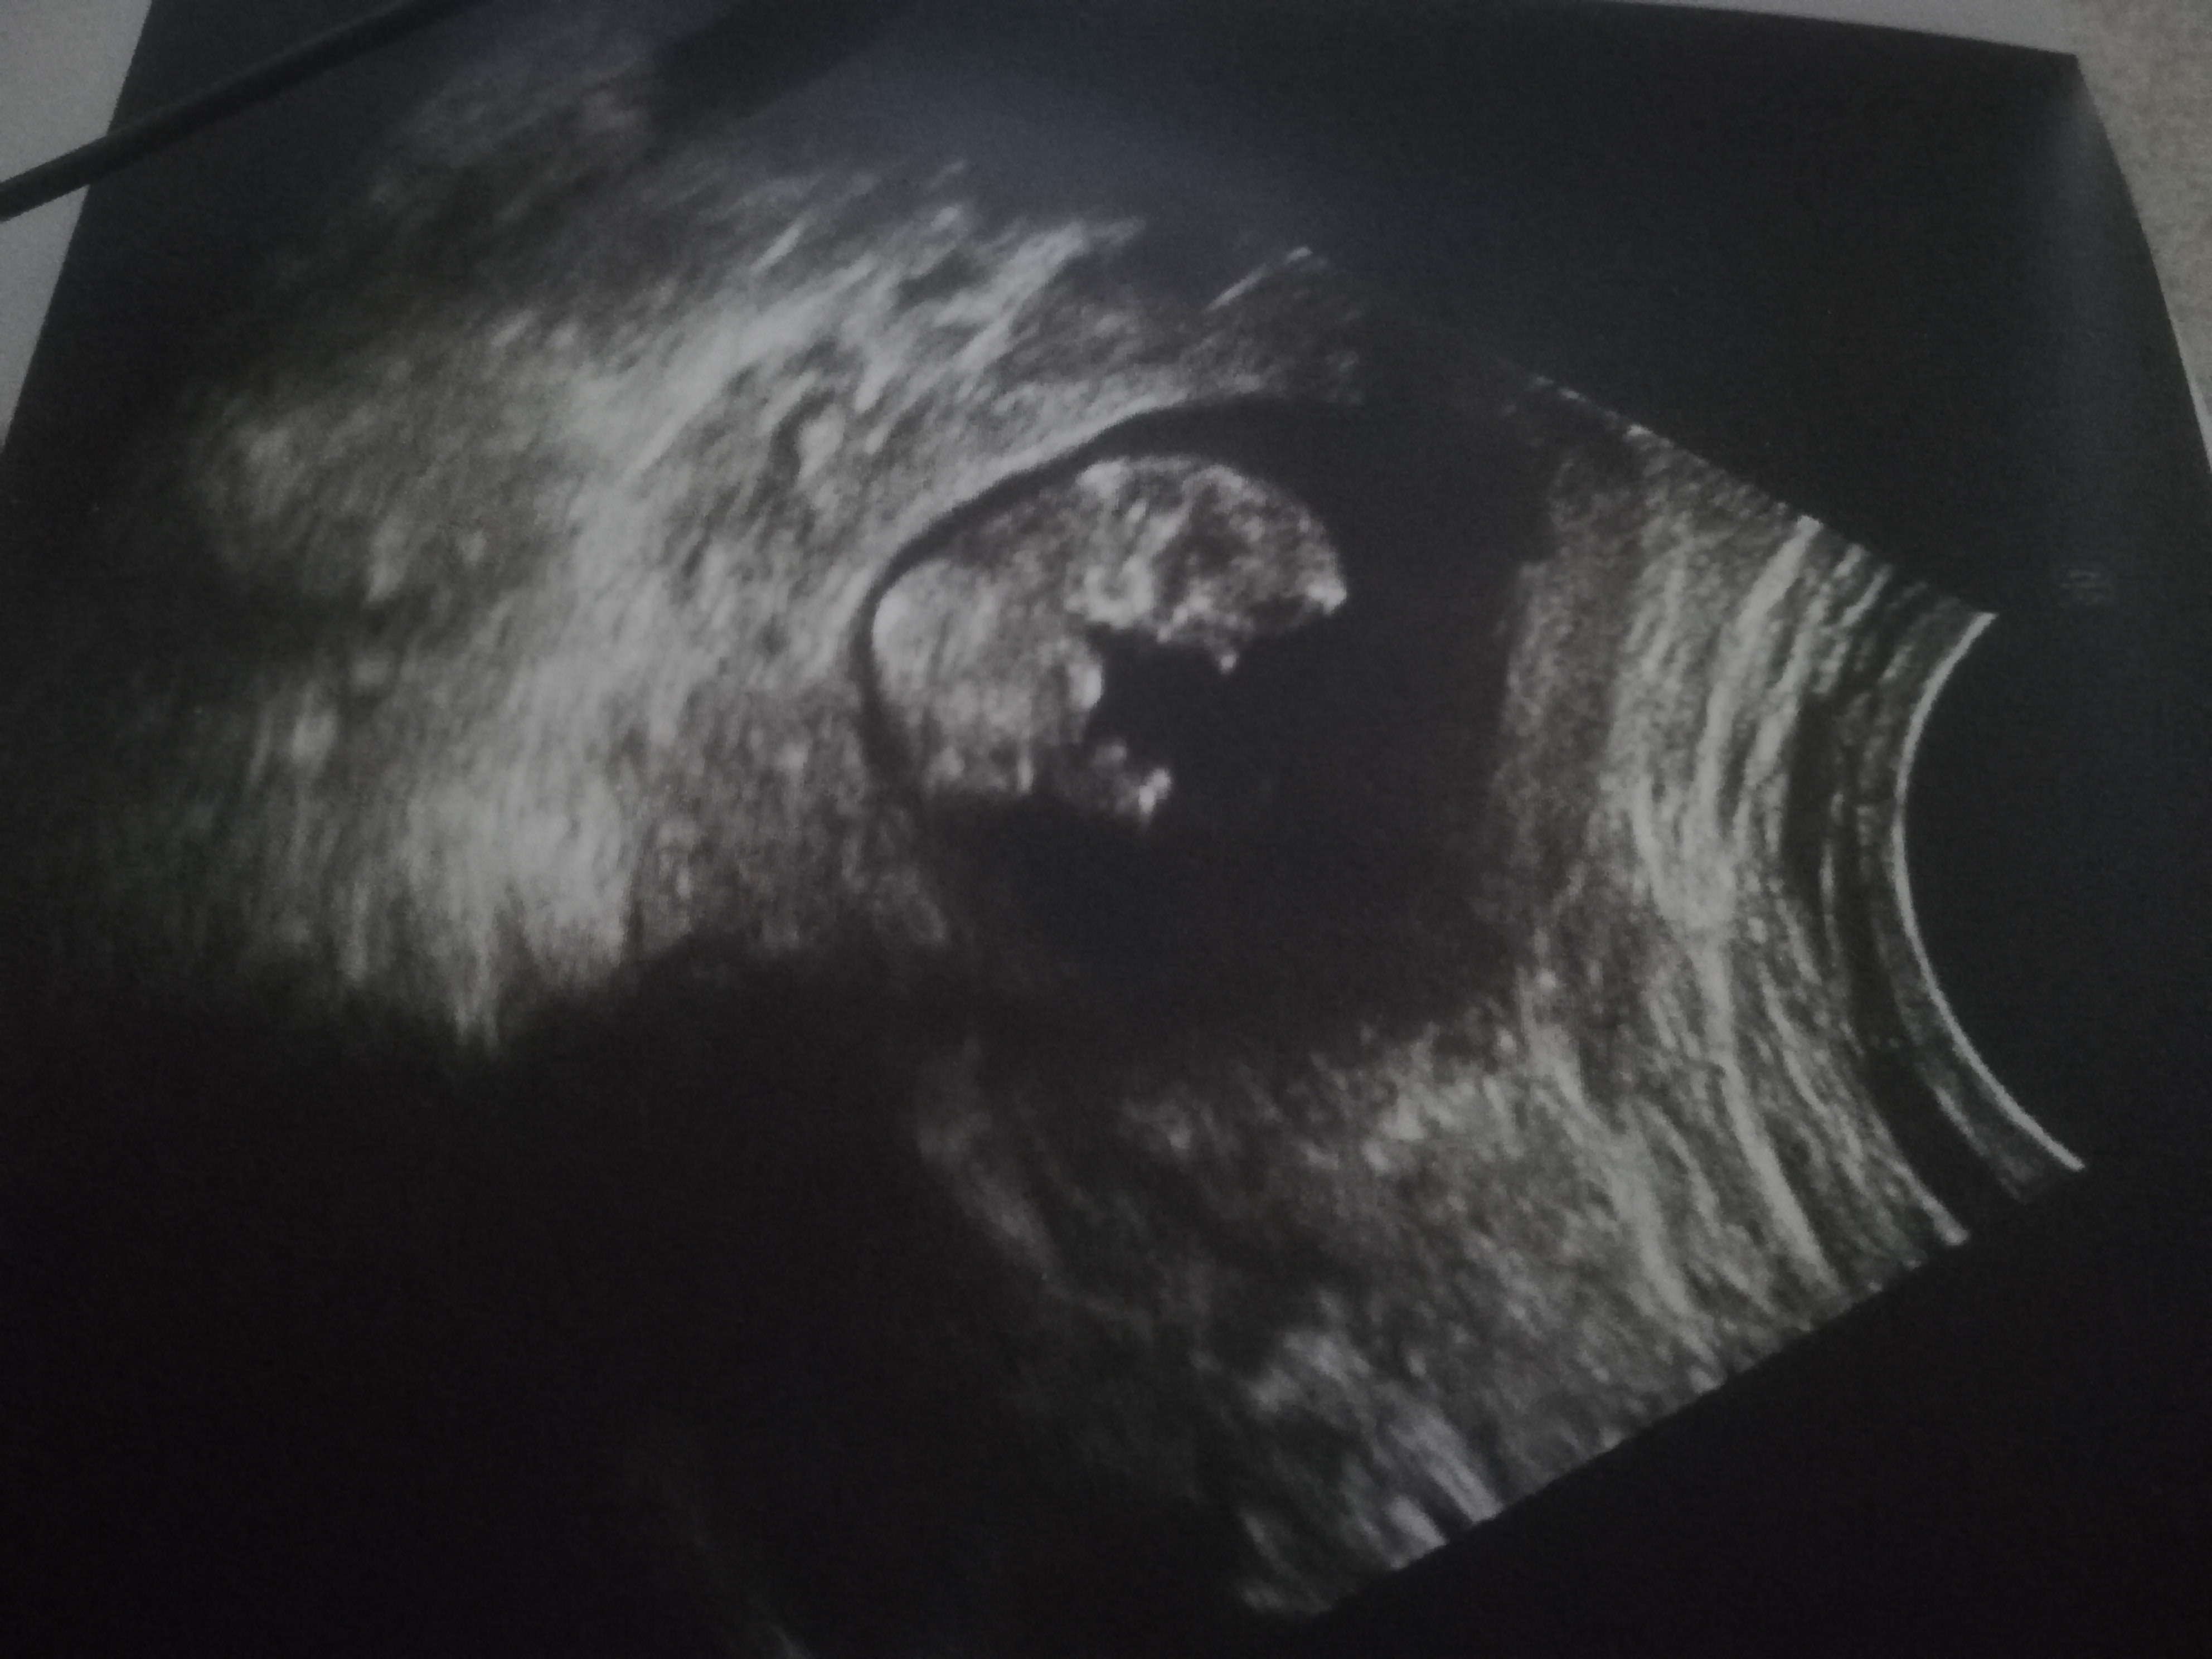

Canim benimkinde bakar mısın 12+1

Ekli dosyalar

• IMG_20211118_153757.jpg

IMG_20211118_153757.jpg

2 MB · Görüntüleme: 255

• IMG_20211118_153746.jpg

IMG_20211118_153746.jpg

1,6 MB · Görüntüleme: 261

• Screenshot_20211118-152347.jpg

Screenshot_20211118-152347.jpg

627 KB · Görüntüleme: 253